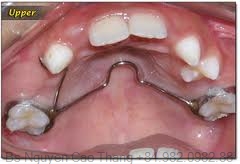

- Hàm giả cố định: Răng giả cố định ở trẻ em là các loại răng giả gắn cố định vào các răng còn lại, có thể là chụp răng hay cầu răng hoặc một biến thể của răng giả tháo lắp.

- Chụp có sẵn dùng cho trẻ em: Là các loại chụp được sản xuất sẵn theo nhiều kích thước khác nhau cho từng loại răng khác nhau.

Chụp có sẵn này có thể được làm bằng thép không gỉ hoặc bằng nhựa carboxylate. Ưu điểm của các loại chụp thép có sẵn là: thao tác nhanh, kết quả tốt, lâu dài hơn so với các phục hồi thông thường, mài răng ít, có khả năng bảo tồn tủy răng cao, giá rẻ, tránh được sâu răng tái phát, giữ được chiều cao khớp cắn, đặc biệt trong các trường hợp bất thường cấu trúc gây mòn răng nhanh, giữ được chiều dài cung răng.

Chỉ định của chụp thép có sẵn: răng sau khi chữa tủy hoặc lấy tủy buồng, răng bị sâu nhiều mặt, răng bị vỡ lớn, răng chấn thương, làm trụ cho hàm giữ khoảng cố định hay tháo lắp hoặc đeo hàm giả, bất thường cấu trúc răng (sinh men bất toàn, sinh ngà bất toàn), dự phòng đa sâu răng và sâu răng tái phát ở các trẻ em có nguy cơ sâu răng cao hoặc trẻ khuyết tật khả năng vệ sinh răng miệng kém. Đối với các răng sữa được lấy tủy buồng, việc phục hồi thân răng bằng các loại chụp là hết sức cần thiết để tránh sự thâm nhiễm nước bọt và/hoặc tránh vỡ thân răng.